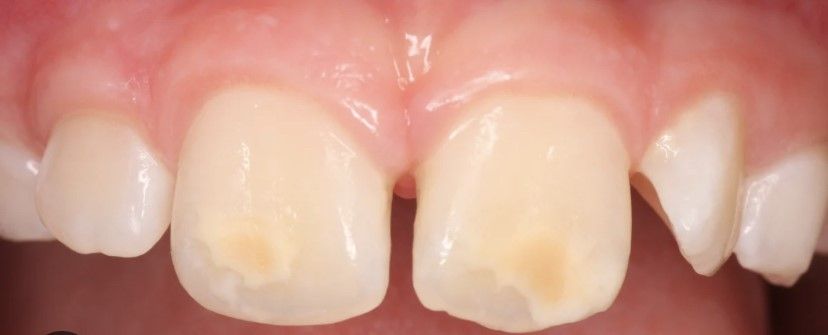

Segurament coneixeu algú o heu vist algun nen/a amb unes taques blanquinoses/groguenques/marronoses en els incisius, normalment els superiors. Aquestes tincions s’anomenen Hipomineralitzacions i afecten d’un a quatre molars i està associat amb algun incisiu afectat, que són els més fàcils de detectar per ser més visibles.

La clínica dental de Sant Cugat Saldana i Fetscher pot tractar les hipomineralitzacions. FOTO: Cedida